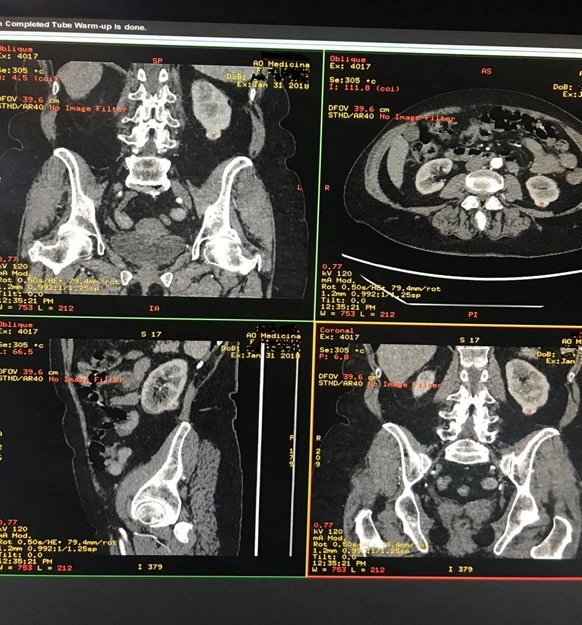

Мультиспиральная компьютерная томография (МСКТ) мочеполовой системы с в/в контрастированием. Отмечается субкапсулярное образование в нижнем полюсе левой почки по задней поверхности (19×14×16 мм, плотность 34 HU), в артериальную фазу накапливает контраст до 134 HU, больше по периферии, в венозную фазу – 101 HU, в отсроченную фазу – 67 HU. Окружающая клетчатка не изменена.

Чашечно-лоханочная система и мочеточники не расширены, рентгеноконтрастных конкрементов не выявлено. Почечные артерии и вены не изменены.